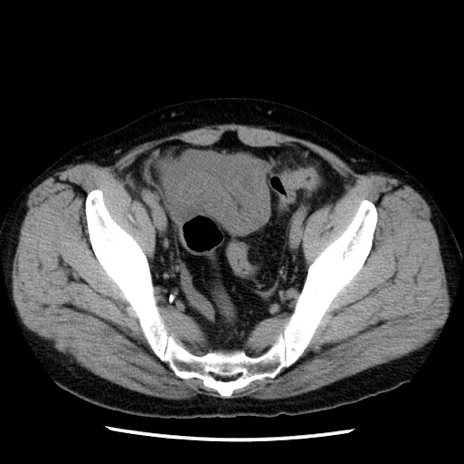

症例29(横断像)

【症例】40歳代男性

【現病歴】2日前から胃痛あり。徐々に周期的な激痛に変化した。本日になっても激痛があるため受診。

【身体所見】意識清明、BT 38-39℃台あり、腹部:膨満、やや硬、右下腹部に圧痛あり。

【データ】WBC 8500、CRP 23.26